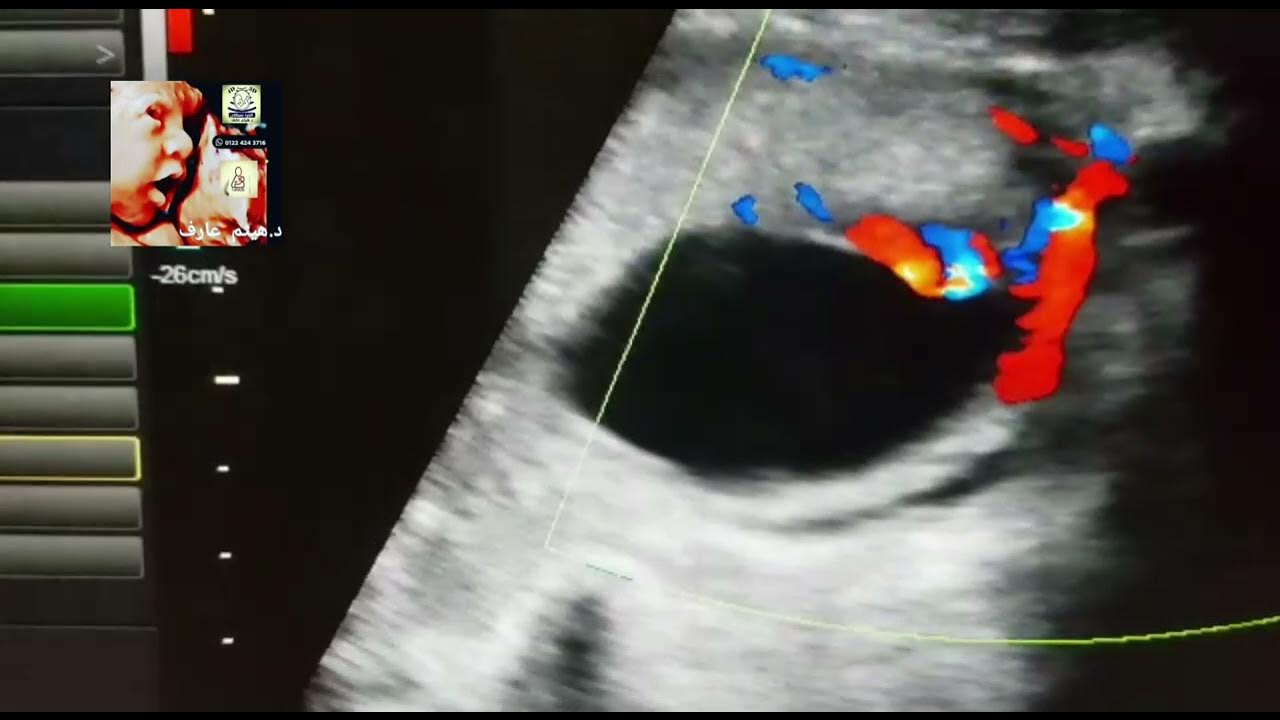

(a,b) Marginal insertion of the umbilical cord seen by color Doppler Marginal Cord Insertion Exercise learn about marginal cord insertion (mci), a rare condition that affects the umbilical cord attachment to the placenta. marginal cord insertion was diagnosed in 163 cases; marginal cord insertion is when the umbilical cord attaches to the side of the placenta instead of the center. 70 cases had a placental cord insertion distance of ≤1.0 cm, and. Marginal Cord Insertion Exercise.

marginal cord insertion ultrasound by Dr.Haissam Aref, DMS, MSc, MD Marginal Cord Insertion Exercise the european association of perinatal medicine (eapm) provides guidelines on screening, diagnosis and management of congenital anomalies. here, the higher risk that marginal cord insertion poses for pregnancy, regarding several adverse outcomes,. learn about marginal cord insertion (mci), a rare condition that affects the umbilical cord attachment to the placenta. 70 cases had a placental cord insertion. Marginal Cord Insertion Exercise.